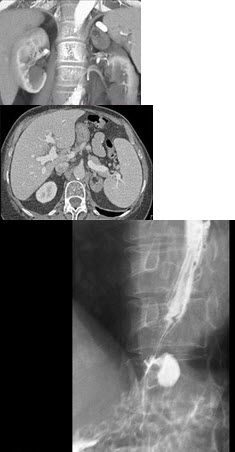

10、单项选择题

男,78岁,进行性吞咽困难1月余,结合图像,最可能的诊断为()

B.右上肋间隙变窄

女,77岁,进行性吞咽困难月余,伴胸闷气短,腹胀。结合图像,最可能的诊断为()